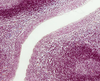

arrows

epithelial reticular cell (of cortex of thymus)

thymic corpuscle (thymus)

coricomedullary junction

bottom line

capsule (thymus)